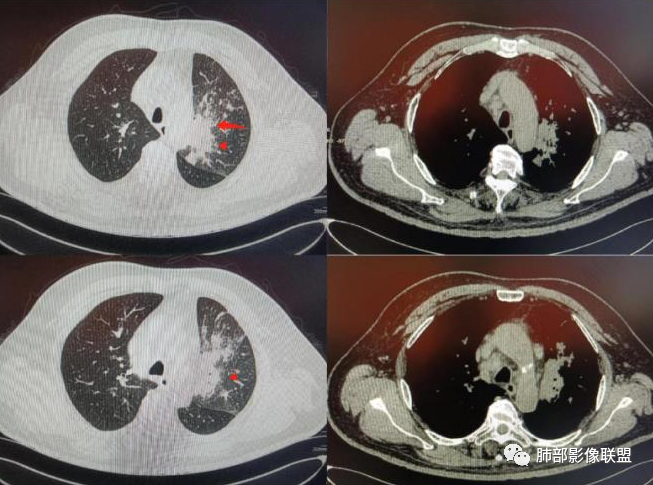

南边:这些是中轴间质增厚?树芽征?

Coke with ice:潘老师,这里是小叶间隔吧?串珠样的。

南边:是的。

南边:尖后段弥漫小叶间隔,中轴间质增厚,部分有结节感,大家考虑啥。

Coke with ice:我觉得是典型的癌淋,较大范围的,比如叶分布,甚至是整个单侧肺,单侧的肺小叶间隔增厚,极大概率是癌淋,另外一个疾病谱就是负压性肺水肿。

Coke with ice:这里有点像原发。隆突下也有大淋巴结。